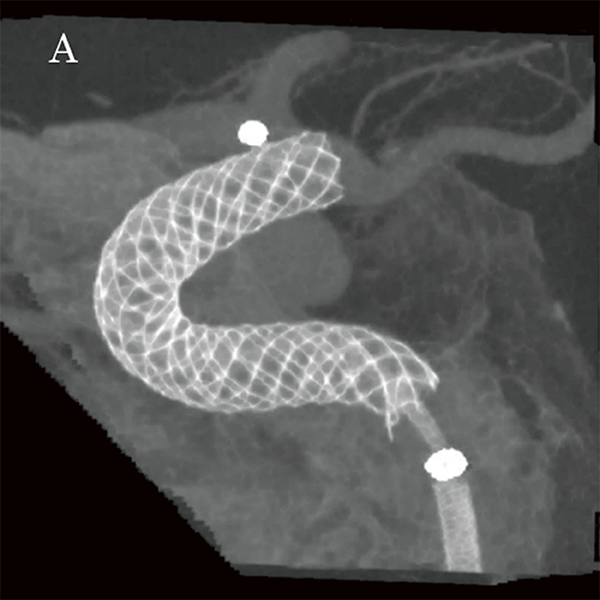

На основі цих вимірювань було обрано пристрій для емболізації Pipeline™ (PED) (4,75 мм × 16 мм; Medtronic, Японія), аневризму лікували, спостерігаючи за флюорографічними зображеннями детектора високої чіткості (мал. 5A та 5B). Пристрій було розгорнуто від C2 (біфуркація задньої сполучної артерії) до C4, а розгортання FD і стан кримпування материнської судини підтверджено Alpha CT (мал. 6A і 6B).

Малюнок 6A: Проекція максимальної інтенсивності Alpha CT після розміщення FD.